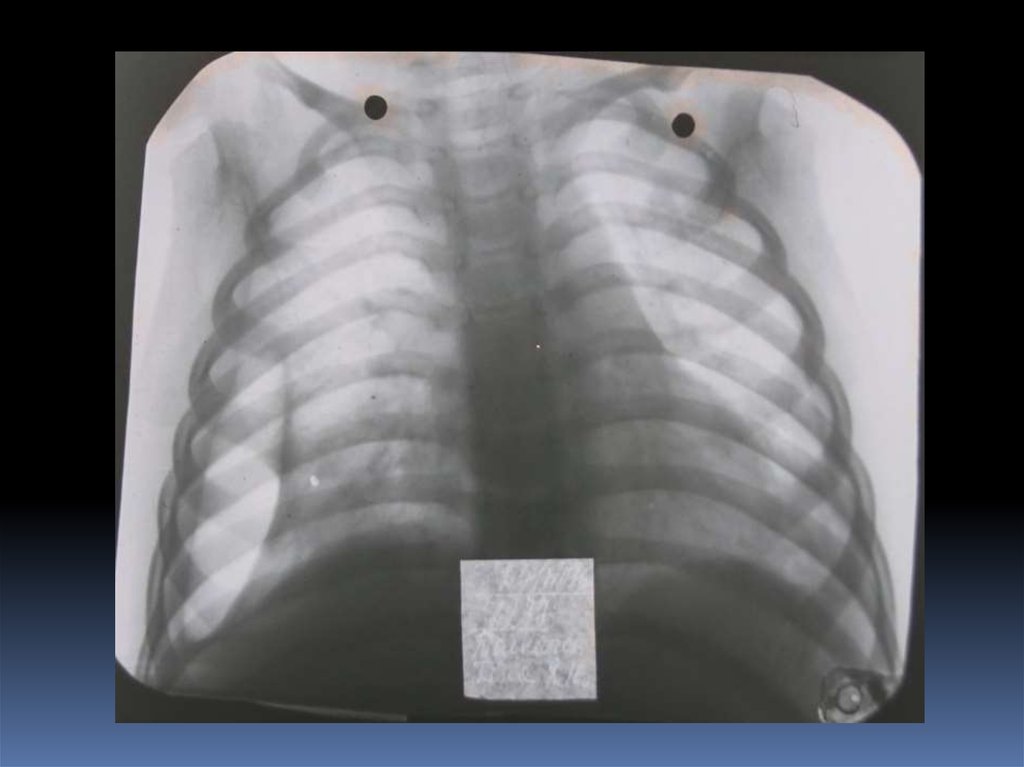

5. Проведение рентгеноскопического исследования раненого.

6. Проведение рентгенографического исследования раненого.

7. Виды травматического повреждения грудной клетки:

пневмоторакс;

гемоторакс;

гемопневмоторакс;

внутрилегочные гематомы;

дисковидные ателектазы;

посттравматические пневмонии.